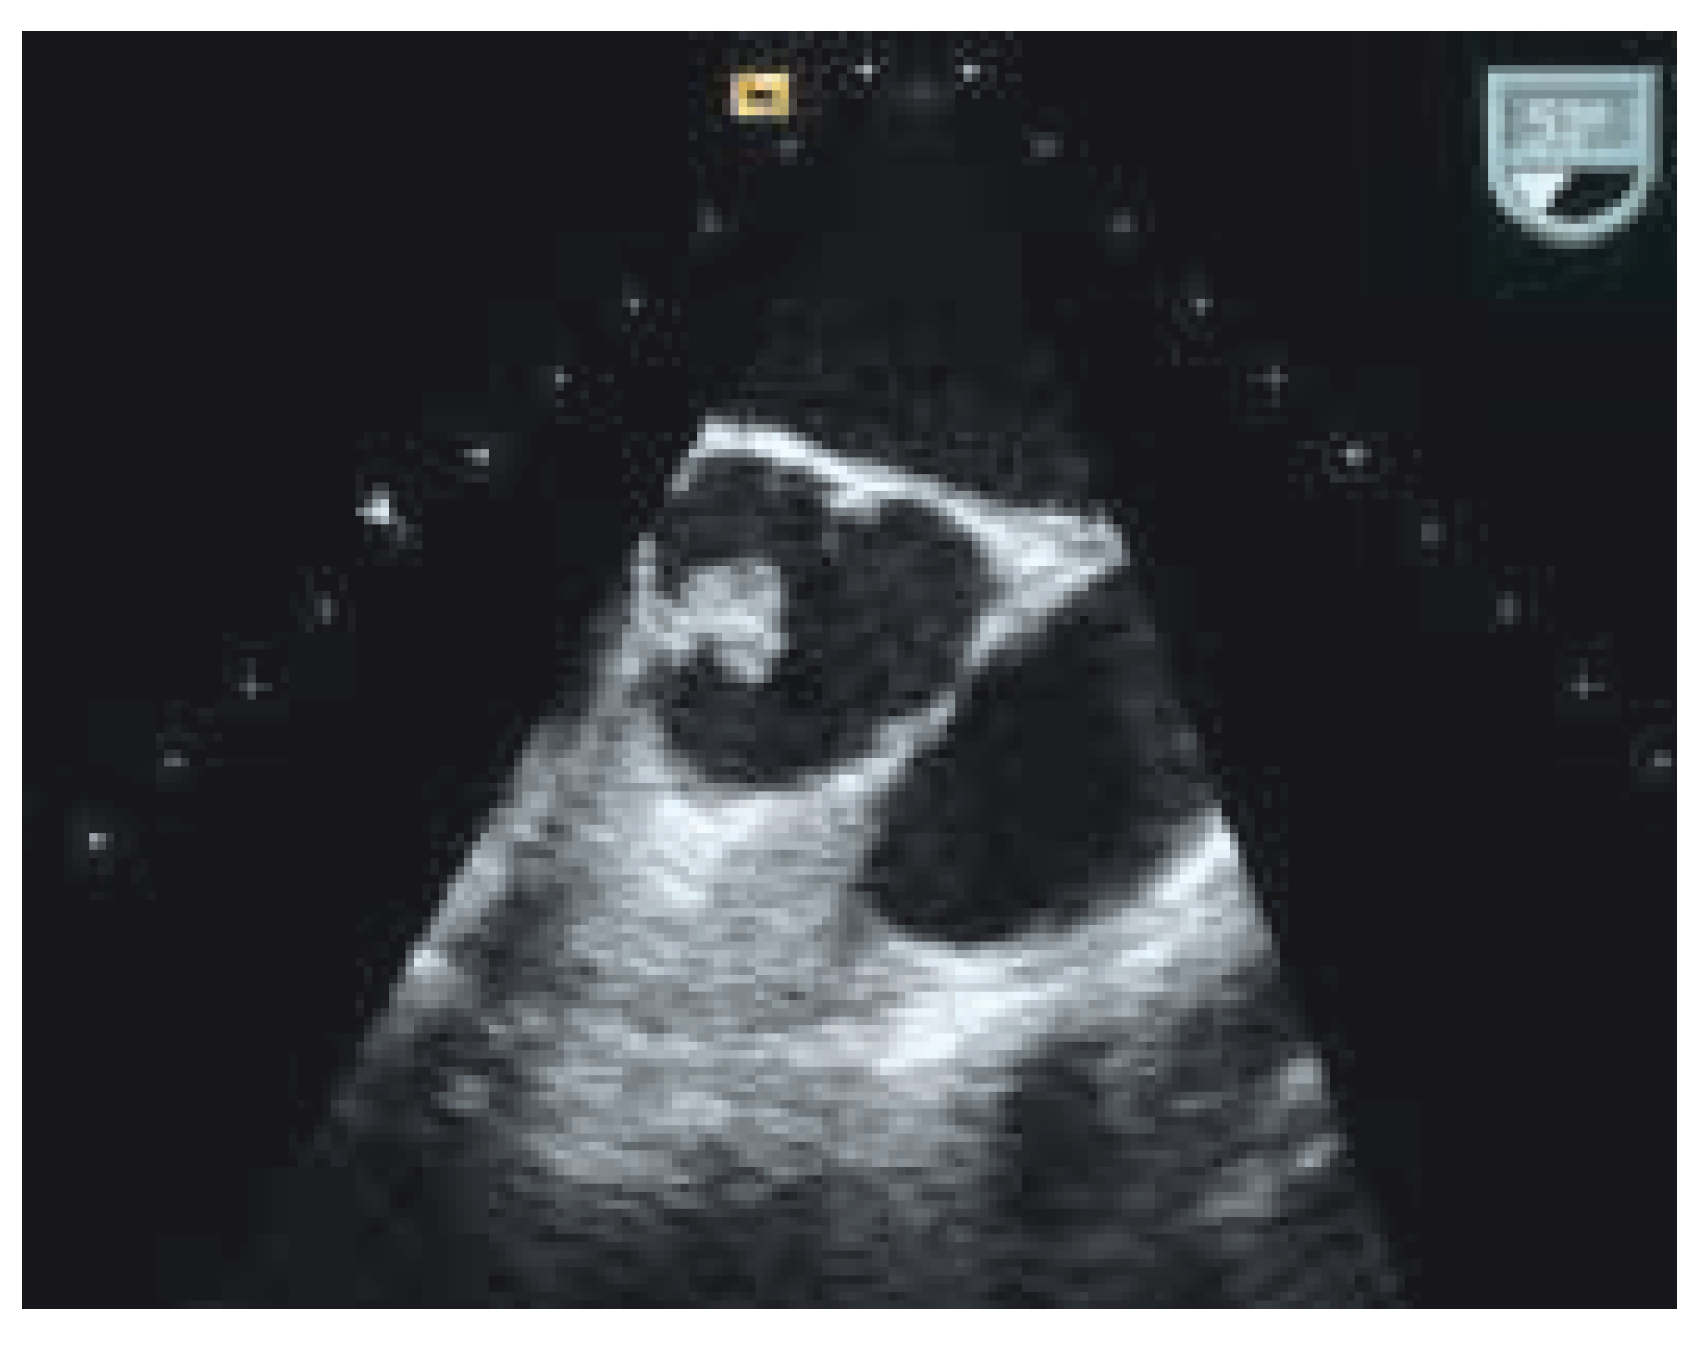

Kardiales Papilläres Fibroelastom

Fallbeschreibung